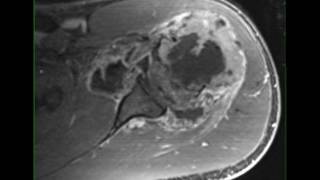

Tumors and tumorous conditions of the bones and joints

Кости → Опухоли